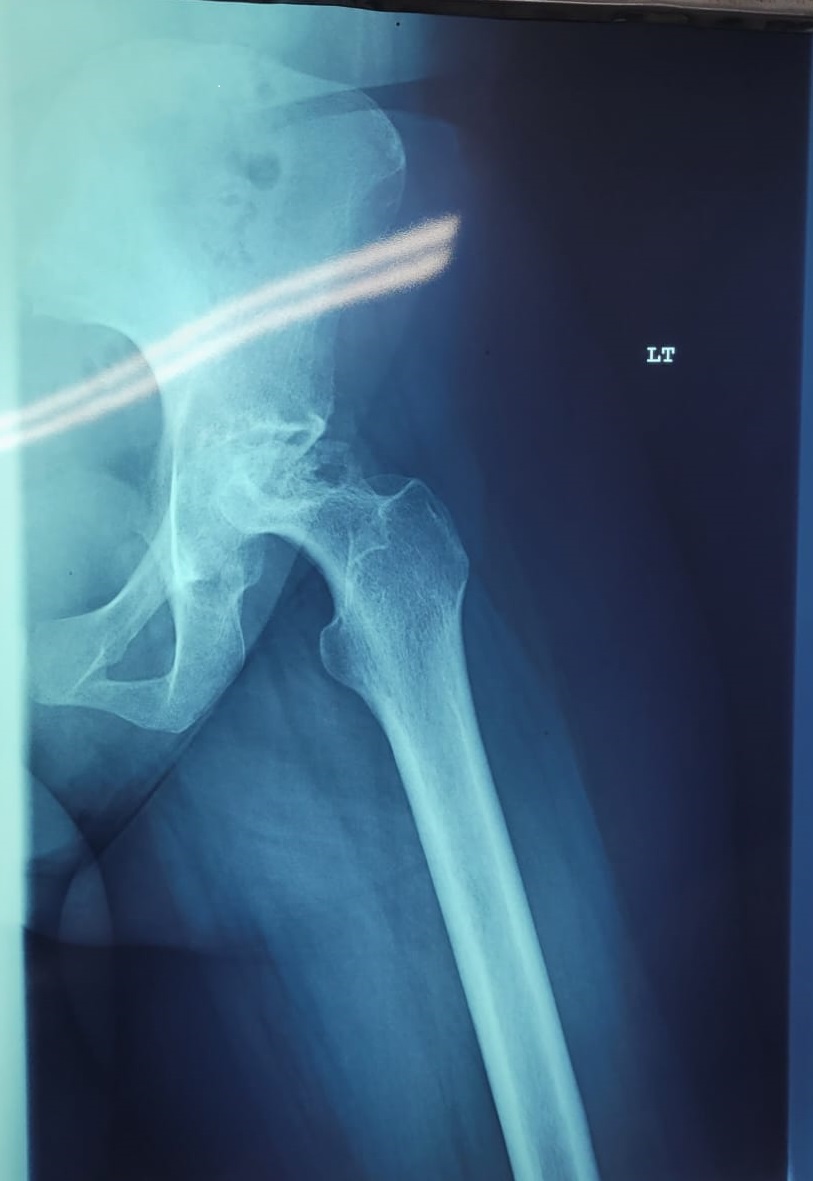

Patient 23

38 year old with avascular necrosis of the hip

Ceramic on poly articulation